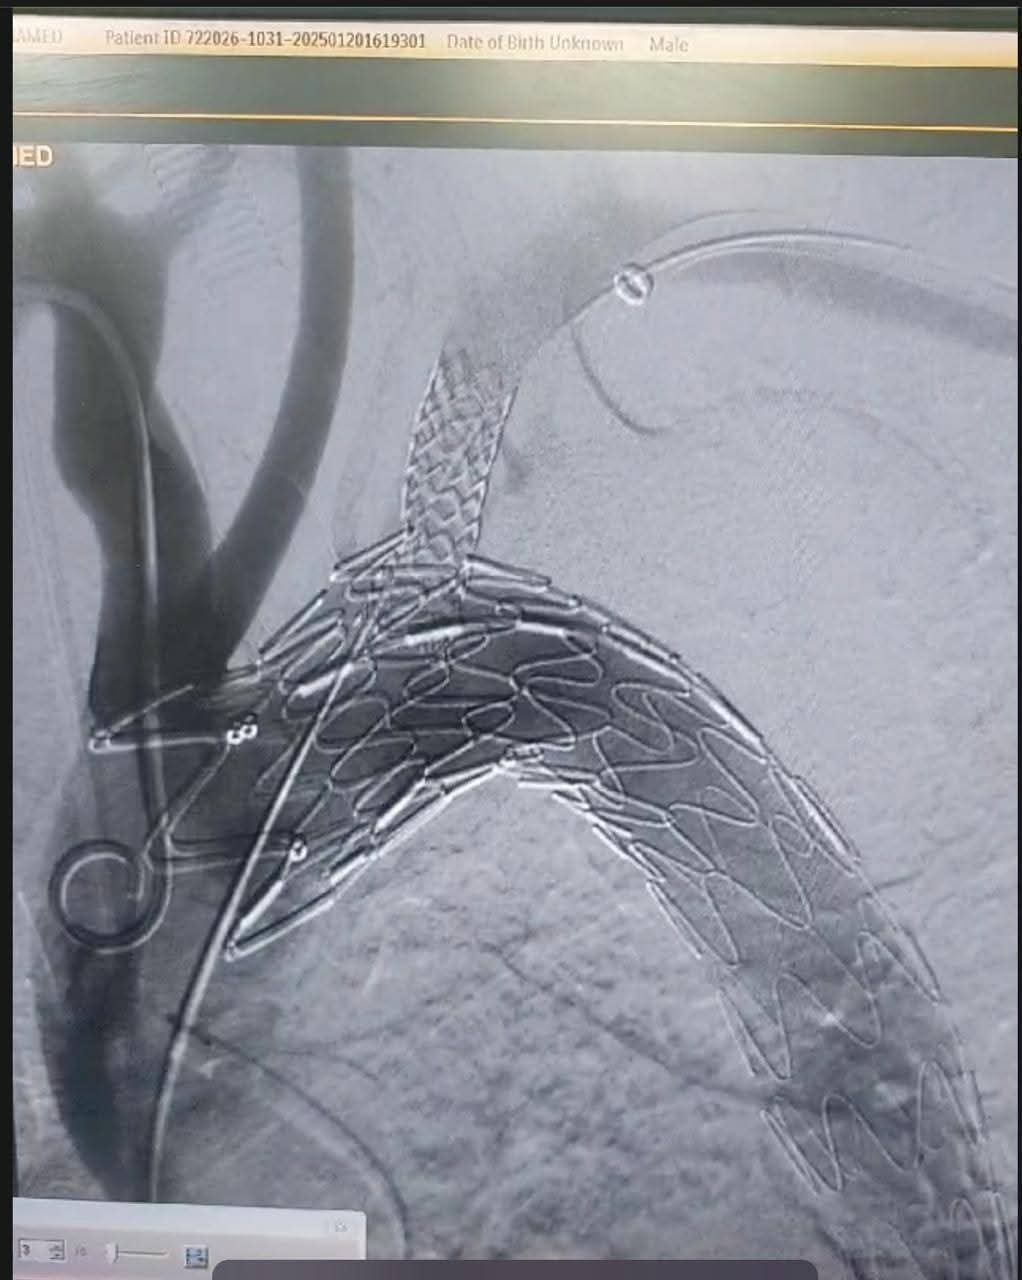

أجرى فريق أطباء قسم جراحة الأوعية الدموية بمستشفي مصر للطيران عملية إصلاح انشطار بالشريان الأورطي الصدري ممتد من الشريان تحت الترقوة الأيسر إلى شريان الحوض والفخذ الأيسر عن طريق استخدام الدعامات المغطاة Ankura™️ لتثبيت الشريان الأورطي الصدري واستعادة تدفق الدم الطبيعي.

وتم استخدام تقنية جديدة تحتاج الي مهارة ودقة عالية وللمرة الأولى في مستشفي مصر للطيران وهي عمل دعامة مغظاة فرعية لشريان الطرف العلوي الأيسر TEVAR + In situ fenestration for LSA + LSA stenting للحفاظ علي الدورة الدموية بالطرف العلوي الأيسر عن طريق عمل فتحة بالدعامة المغطاة بالشريان الأورطي الصدري باستخدام إبرة ( Futhrough™️ ) للحفاظ علي تدفق الدم بواسطة القسطرة التداخلية.